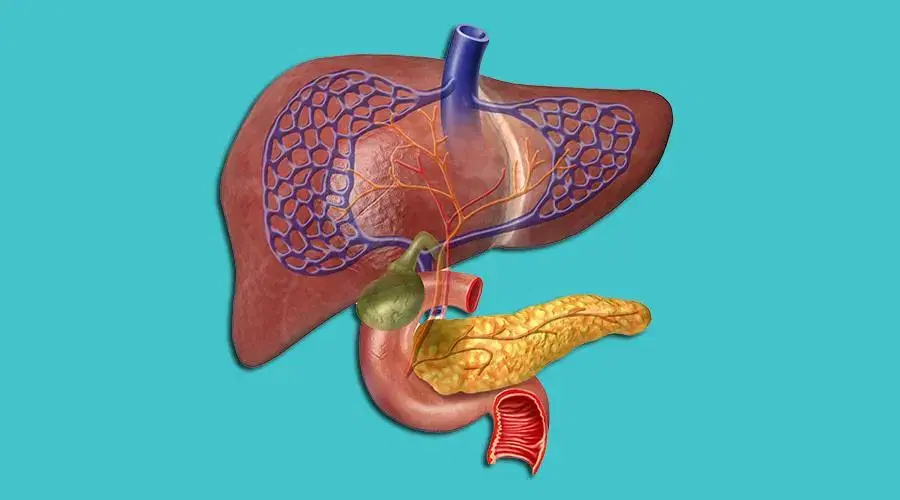

Hepatobiliary and Pancreatic Surgery in Vijayawada

Hepatobiliary and pancreatic surgery focuses on treating complex conditions affecting the liver, gall bladder, bile ducts, and pancreas. At Vijayawada Gastro Centre, our expert surgical team provides advanced care using minimally invasive and laparoscopic techniques for safe and effective treatment. We manage disorders such as liver tumors, bile duct obstructions, gall bladder diseases, and pancreatic cysts or pancreatitis. With state-of-the-art imaging, precision diagnostics, and personalized treatment plans, we ensure accurate evaluation and optimal outcomes. Our specialists are committed to delivering compassionate care, faster recovery, and high-quality surgical solutions for patients with hepatobiliary and pancreatic conditions.

Laparoscopic Liver Surgery in Vijayawada

Laparoscopic liver surgery is a minimally invasive procedure used to treat liver tumors, cysts, and other liver conditions with greater precision and faster recovery. At Vijayawada Gastro Centre, our expert hepatobiliary surgeons use advanced laparoscopic technology to perform complex liver surgeries through small incisions. This approach reduces pain, minimizes blood loss, and allows quicker return to daily activities. We offer comprehensive evaluation, accurate imaging, and personalized surgical plans to ensure the best outcomes. With state-of-the-art facilities and experienced specialists, we provide safe, effective, and compassionate laparoscopic liver surgery for patients in Vijayawada.

Pancreatic Cancer Surgery in Vijayawada

Pancreatic cancer surgery is a highly specialized procedure aimed at removing cancerous tissue and improving long-term outcomes. At Vijayawada Gastro Centre, our expert hepatobiliary and pancreatic surgeons use advanced imaging, endoscopic evaluation, and modern surgical techniques—including the Whipple procedure and distal pancreatectomy—to provide precise and effective treatment. We focus on early diagnosis, complete tumor removal, and comprehensive postoperative care. With minimally invasive options available for select cases, patients experience reduced pain and faster recovery. Our multidisciplinary team ensures personalized treatment plans, compassionate support, and state-of-the-art care for pancreatic cancer patients in Vijayawada.